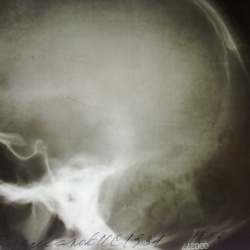

Молодой человек 20-ти лет, призван в ряды ВС,из анамнеза известно, что " мама говорила, что у меня врожденное заболевание черепа".Не обследовался, жалоб нет( кроме равной раны уха).2 дня...